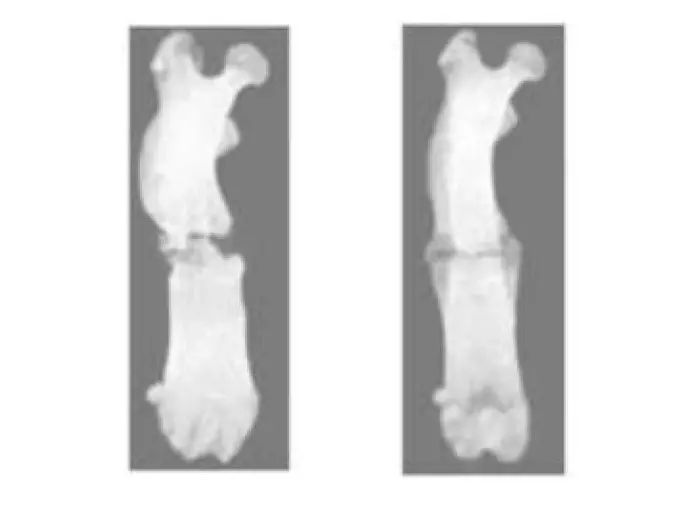

The researchers broke the legs of the rats in two ways. One group of 24 rats had normal fractures that are generally easy to heal. The other group of 20 rats had fractures known as non-union ones where healing is usually prolonged or does not happen. Some were then irradiated with non-thermal atmospheric-pressure plasma, which didn’t offer the normal fracture group any significant advantages but boosted the healing and recovery time of the rats with non-union fractures. The strength of the healed areas of the irradiated non-union rats was also about 3.5 times stronger than that of the nonirradiated ones.